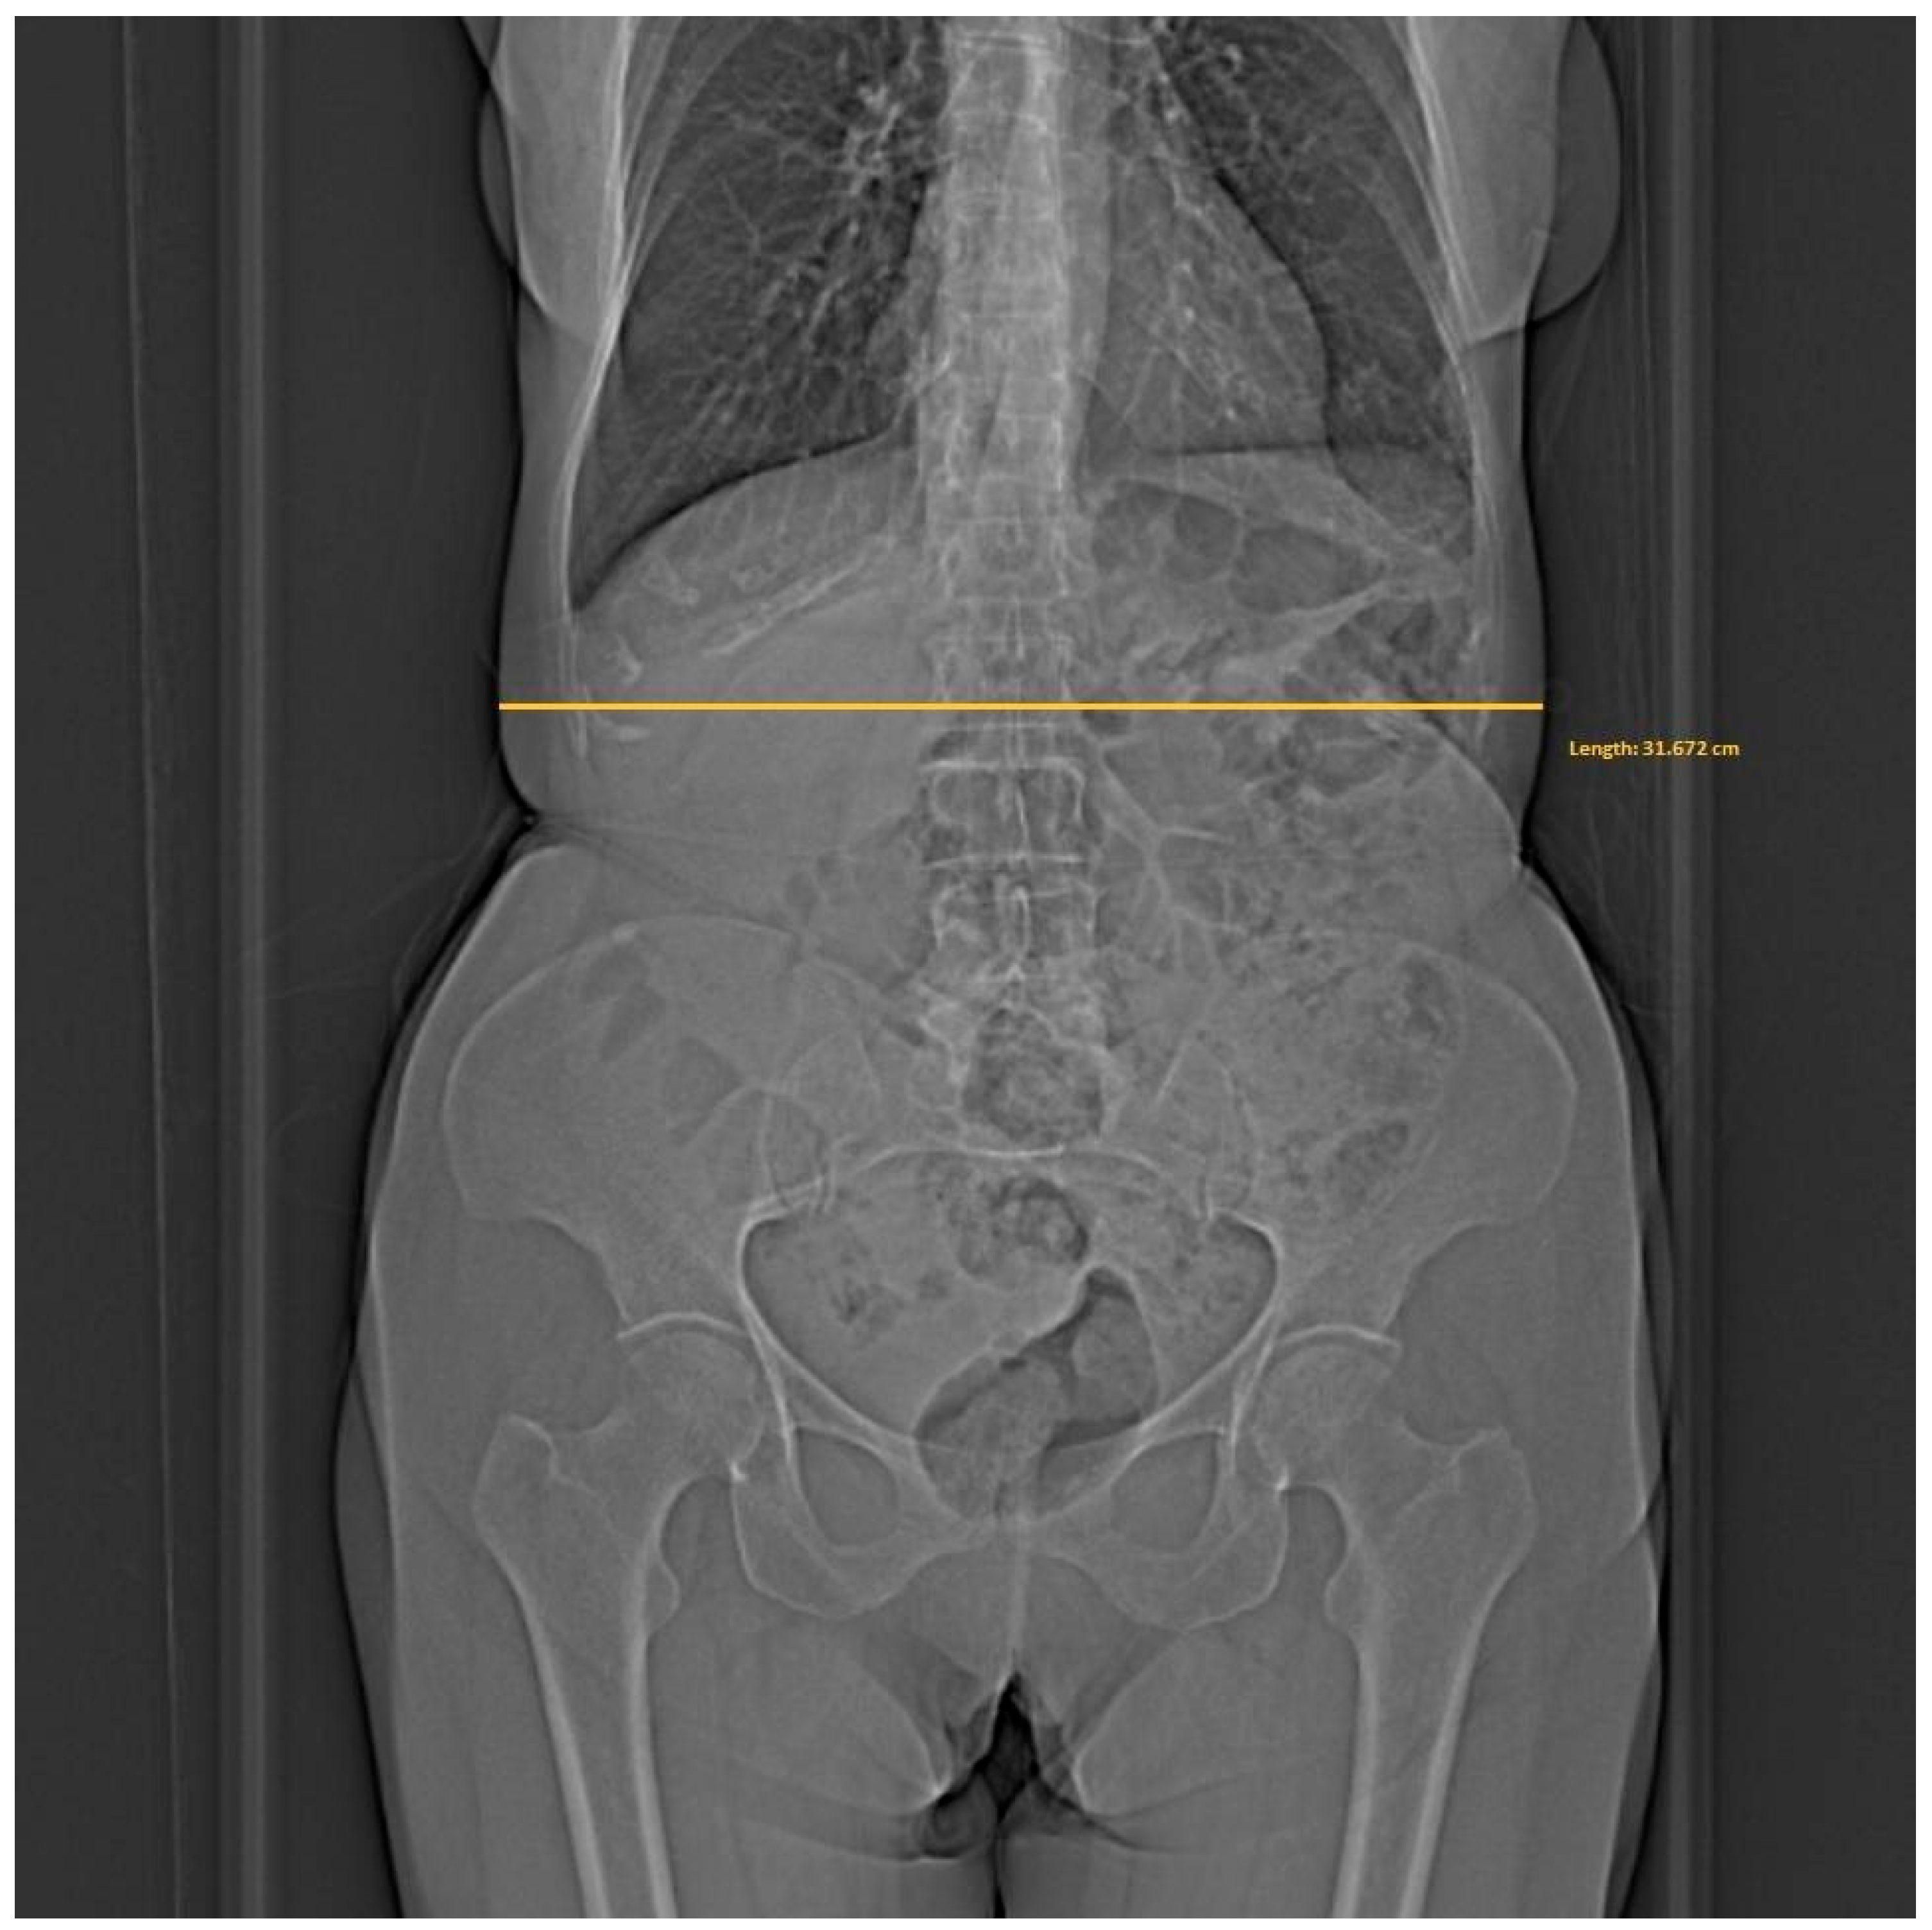

In addition, the widest point in the abdominal area was measured on the patient’s toposcan in the Horos software (4.0.0 RC5). The measurement scheme is shown in Figure 3.

Figure 3.

Diagram for measuring the patient’s widest point based on the toposcan performed.